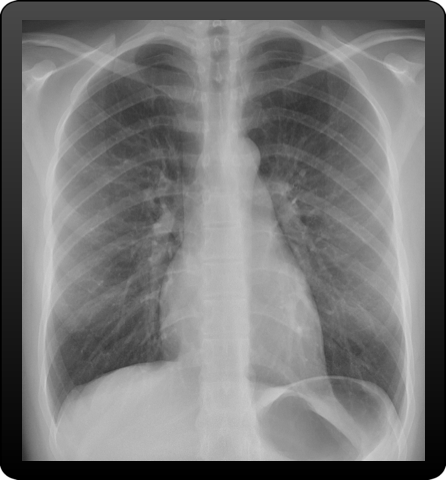

X-ray

Catalog of X-ray images

Get acces to thoracic X-ray images acquired with several acquisitions protocol from different clinical sites

Discover